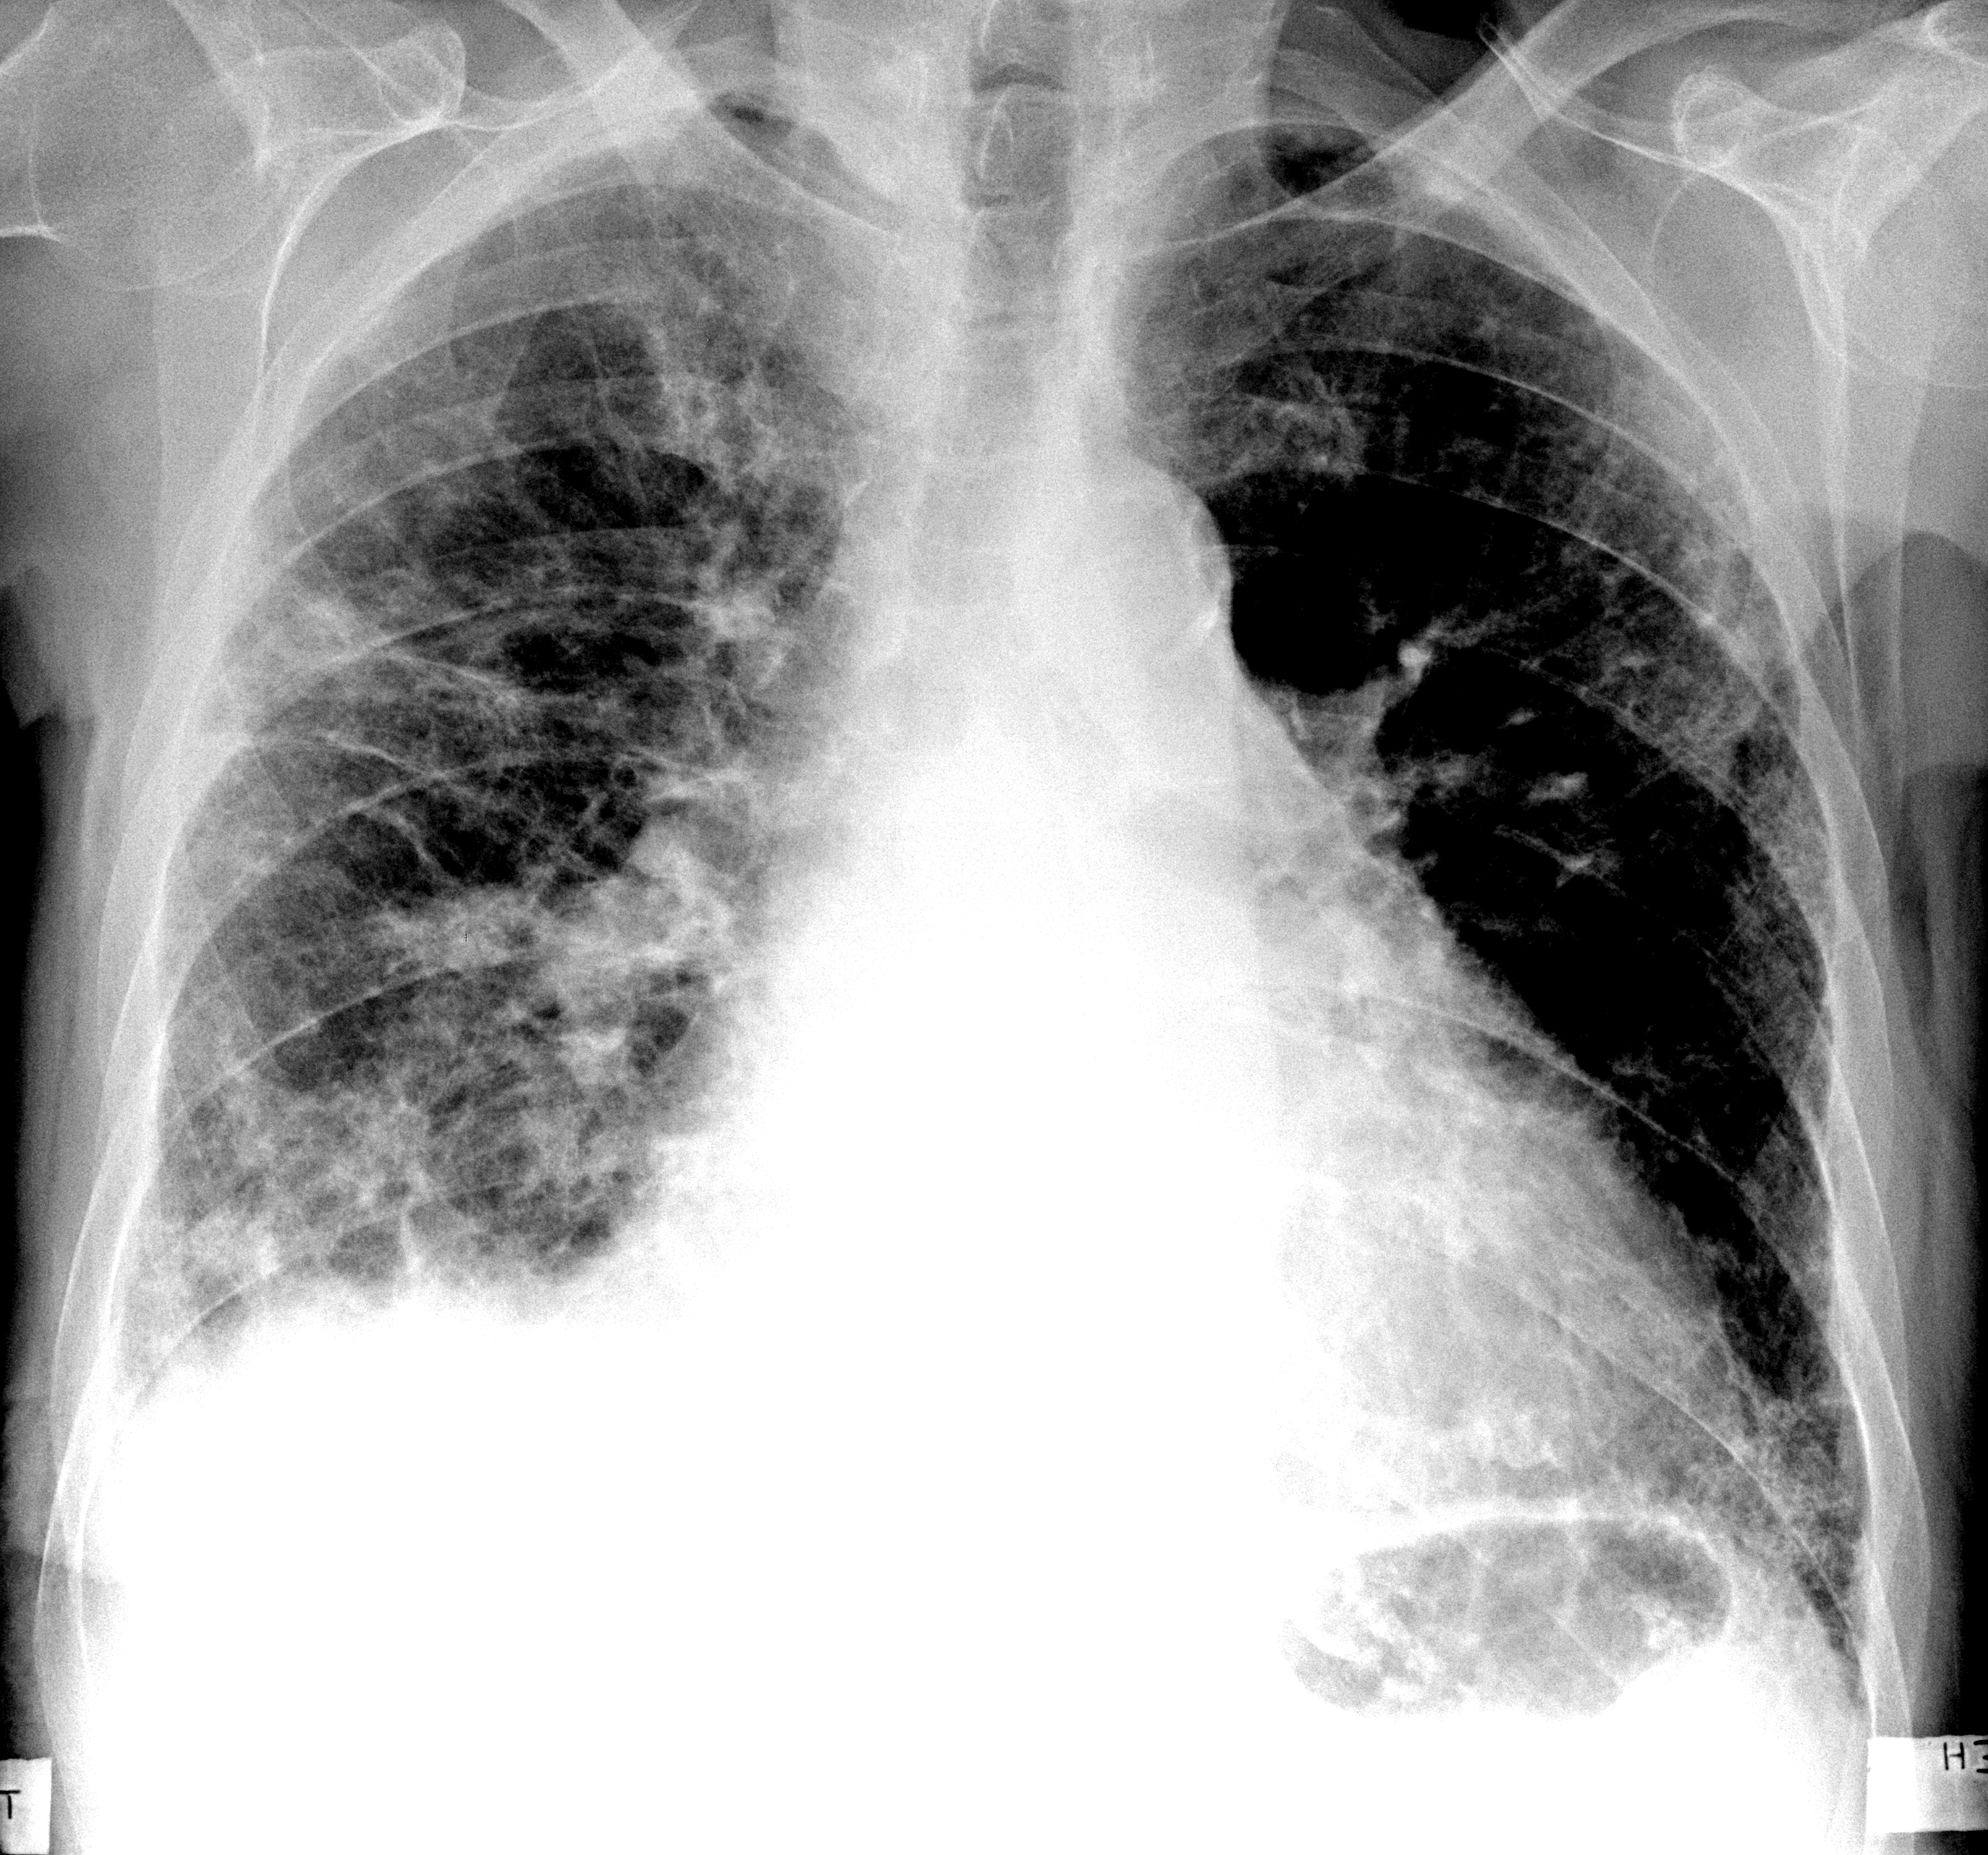

Поражение легких является одним из основных симптомов коронавируса (COVID-19). В данной статье представлены фото рентгеновских снимков, которые позволяют визуально оценить состояние легких при этом заболевании.

Коронавирус пневмония рентген

Рентген легких пневмония коронавирус

Фото рентгеновских снимков поражения легких при COVID-19

На фотографиях рентгеновских снимков видно, как вирус воздействует на легочную ткань. Характерные признаки поражения легких включают пятна, инфильтраты и наличие жидкости внутри легочных альвеол.

Фото рентгеновских снимков помогают врачам и специалистам визуально определить степень поражения легких и принять соответствующие меры лечения и поддержки пациента.